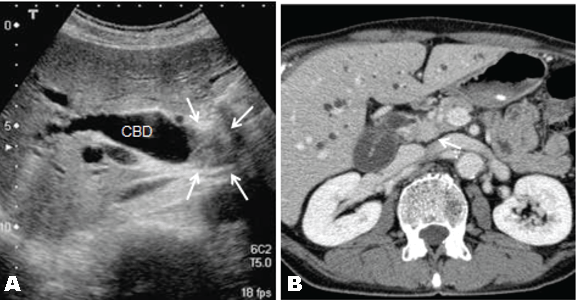

A 67-year-old male patient was referred to our hospital to investigate a case of jaundice on October 2010. He denied anorexia, abdominal pain, alcohol abuse and cigarette smoking. Physical examination revealed a mildly cachectic and icteric male with no acute distress. An abdominal examination revealed no palpable abdominal masses, organomegaly or evidence of ascites. He denied abdominal tenderness. On admission his total bilirubin level 7.52 mg/dL, alkaline phosphatase 1032 IU/L (normal range 105–320 IU/L), carcinoembryonic antigen 11.8 ng/dL (range, 0.0–5.0 ng/dL), carbohydrate antigen 19–9 was 765.1 Um/L (normal range 0.0-37.0 U/mL). Ultrasonography and contrast-enhanced computed tomography (CT) of the abdomen revealed a mass, approximately 2 cm in diameter, in the middle of the common bile duct (CBD), which caused the dilatation of the proximal biliary tract. (Figure 1A–B) Endoscopic retrograde naso-biliary drainage was successfully performed to improve the jaundice. Cholangiography and magnetic resonance cholangiopancreatography revealed a 2.5-cm filling defect in the middle of the CBD. (Figure 2) Based on these findings, the patient was diagnosed with middle bile duct cancer and a subtotal-stomach-preserving PD was planned.

Figure 2: Cholangiography showing a 2-cm filling defect (arrows) in the middle of the common bile duct.